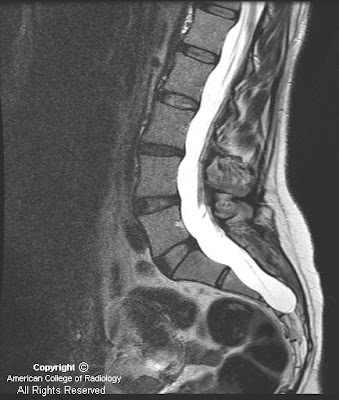

Findings

Figure 1 and Figure 2: Axial and sagittal CT images demonstrate dural ectasia with a capacious thecal sac to the level of the sacrum.

Figure 3 and Figure 4: Sagittal T1 postcontrast and T2-weighted MR images reveal a dilated terminal thecal sac without a tethered cord. Benign subtle scalloping of the posterior margin of the lumbar and sacral vertebral bodies (Figure 4) is best visualized on the T2-weighted images.

This case is an example of an expanded dural sac with posterior vertebral scalloping of the lumbar spine and sacrum. Findings include a capacious thecal sac with smooth scalloping of the posterior aspect of the involved vertebral bodies. Dural dysplasia most often occurs in the lumbar spine but can involve the cervical and thoracic spinal canal as well. The case described herein is mild as there is no resulting kyphoscoliosis or erosion of the pedicles which occurs in more severe cases. Making the diagnosis of dural dysplasia requires that one excludes other causes of the expansion of the canal such as syrinx, tumor or meningeal cyst. The differential diagnosis and etiology of dural dysplasia is extensive and should be distinguished from meningeal cysts. The patient in this case had no known cause for the dural dysplasia and only complained of back pain.